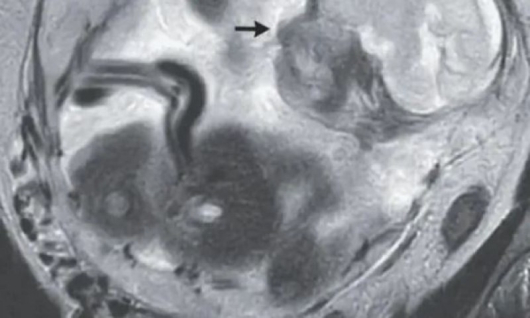

37-годишна жена от Франция, отишла на лекар след десет дни на силни коремни болки и подувания на стомаха, се оказва с особена бременност - плодът се развивал в черво. Първоначалният преглед показал, че бъдещата майка е бременна в 23-та седмица. А с допълнителен ултразвук лекарите установили, че матката на жената е празна и тя има "рядък тип извънматочна бременност", съобщава британското специализирано идание New England Journal of Medicine.

При абдоминалната бременност оплодената яйцеклетка се имплантира извън матката в коремната кухина – понякога върху черния дроб и червата. Това се случва само при един процент от всички извънматочни бременности и е животозастрашаваща. Тя може да доведе до вътрешен кръвоизлив, спукана фалопиева тръба или шок на организма. Много рядко и плодът успява да оцелее.

Поради възможни усложнения след диагностицирането младата жена е преместена в университетска болница, където бебето извадено в 29-ата седмица от бременността и са полагани специални грижи за него. По-късно и майката, и бебето са изписани в добро общо състояние.